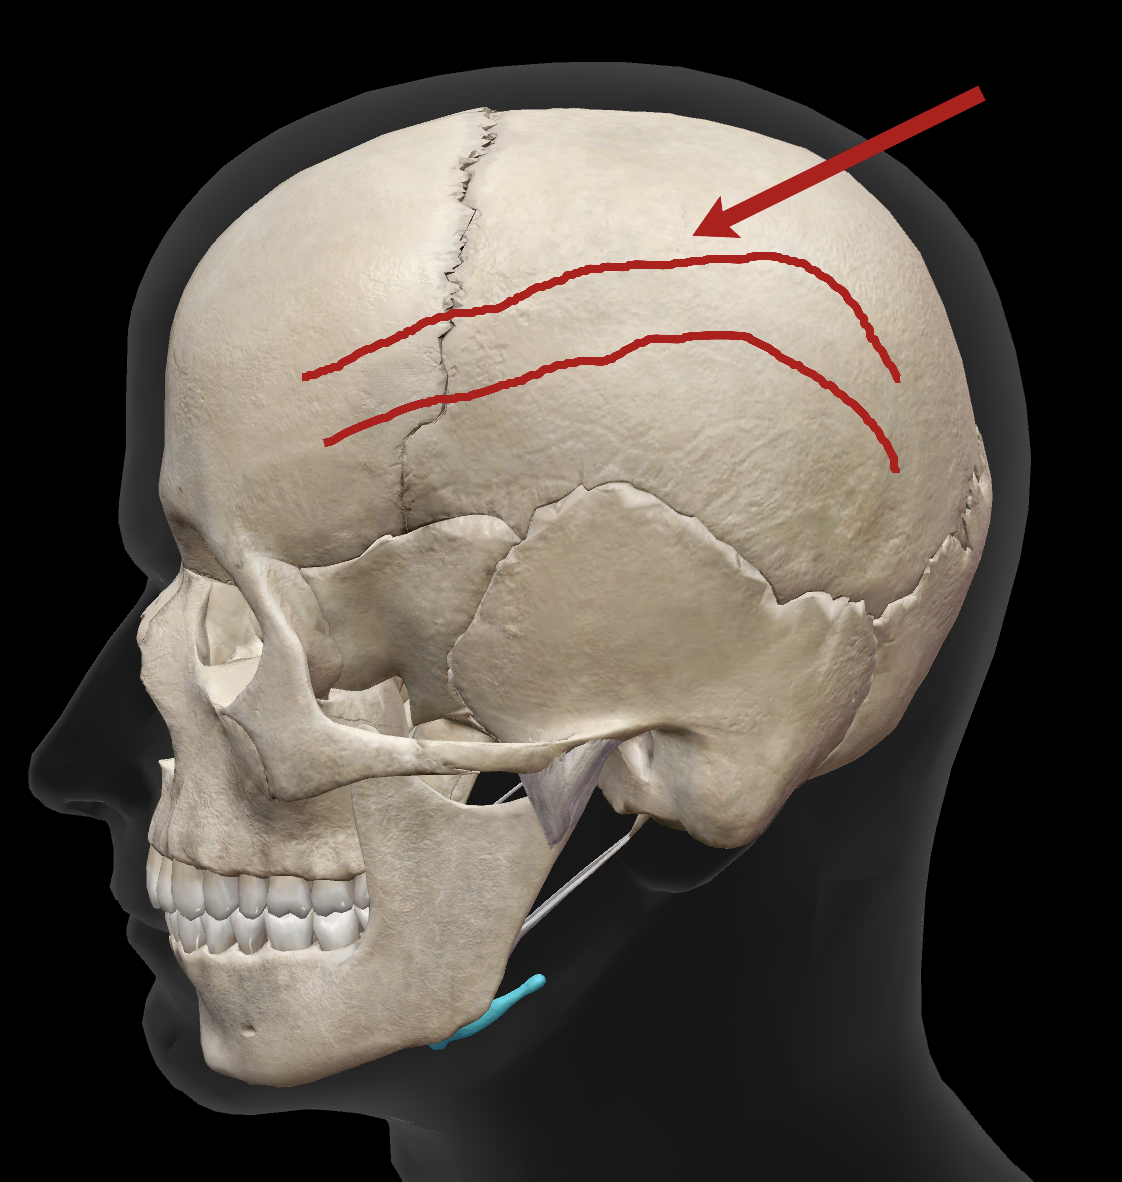

What is the name of this suture?

coronal suture

What is the name of this feature?

superior temporal line

What is the name of this feature?

inferior temporal line